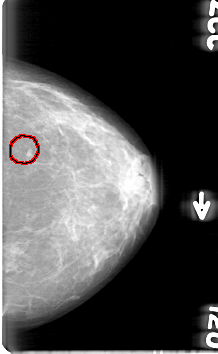

D_4057_1.RIGHT_MLO

LEFT_MLO LINES 5281 PIXELS_PER_LINE 3061 BITS_PER_PIXEL 12 RESOLUTION 43.5 OVERLAY

FILE: D_4057_1.LEFT_MLO.OVERLAY

TOTAL_ABNORMALITIES 1

ABNORMALITY 1

LESION_TYPE MASS SHAPE IRREGULAR MARGINS OBSCURED

ASSESSMENT 0

SUBTLETY 3

PATHOLOGY BENIGN

TOTAL_OUTLINES 1

BOUNDARY